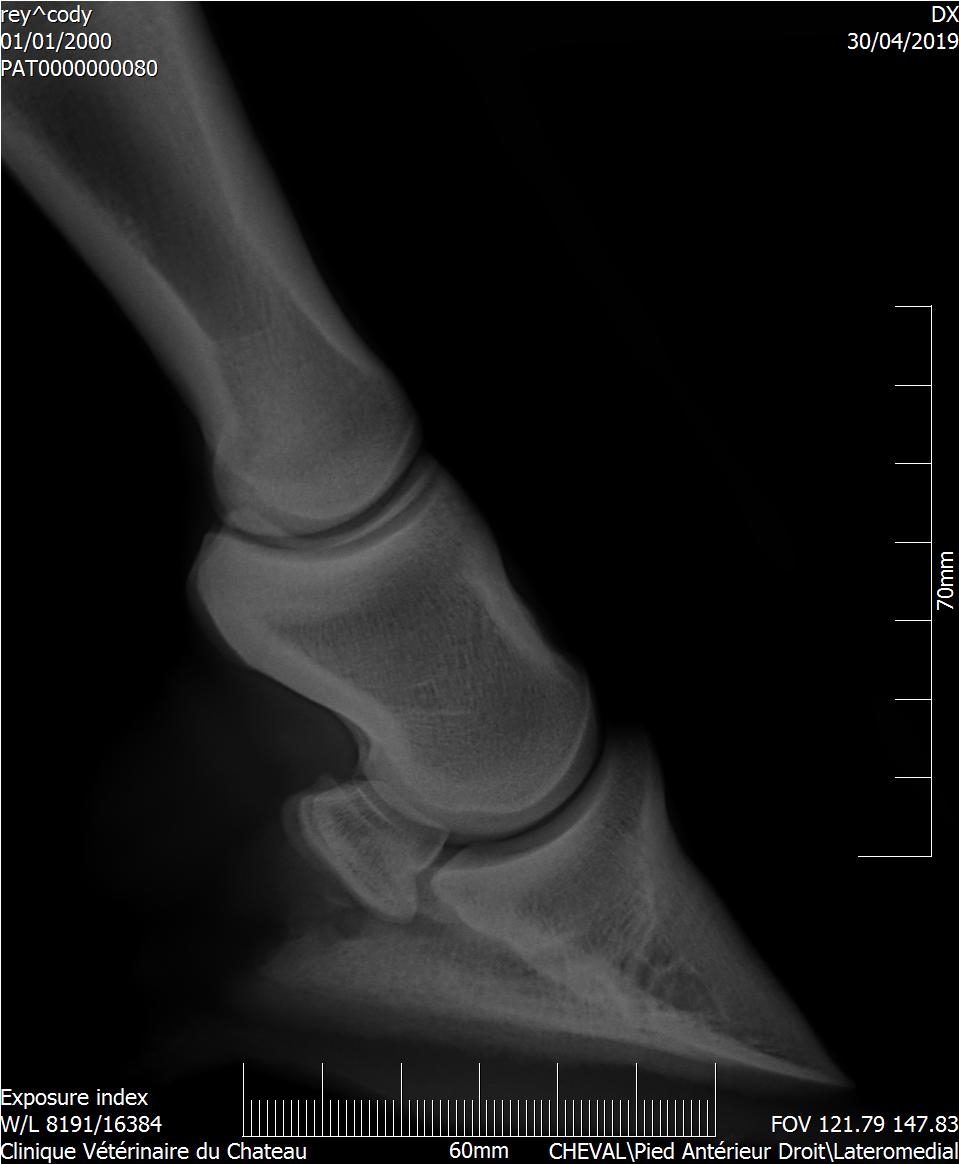

| Dire merci | Bonjour J'ai fait un bilan radio à ma mule qui est irreguliere pour recherche de la cause de sa sensibilité. Le veto m'envoie ce cliché de profil. C'est moi où on ne peut juger de l'épaisseur de la sole et que c'est le premier truc à regarder dans pareil cas ? Merci par avance pour vos avis éclairés... j'en ai d'autres de face et derrière si certains seraient capable d'évaluer la sole... Quand je demande au veto qui me parle absolument pas de pb de sole il me répond évasif "Ah oui peut être un peu fine" ![]() ![]() Édit: ajout photo de dos Message édité le 29/07/19 à 19:52 [edit modo suppression coordonnées véto] Ce message a été modifié par un modérateur. |

| Dire merci | Si : ras sauf légère demineralisation de P3 . Tester réaction aux AI Donc bon moi je veux bien hein mais la première chose à savoir et surtout si la seule anomalie est sur la phalange c'est est ce qu'elle est protégée convenablement... Non? J'espère avoir tort c'est pas mon métier mais je n'ai malheureusement pas assez confiance. Donc même si il se trompe sur le diag c'est pas tellement grave, mais je paye pas un photomaton qui me prend la moitié du visage. Donc c'est ma question ... cette radio est elle acceptable dans le cas d'une recherche d'explication pour pied sensible? |

| Dire merci | Franchement je lui demanderai de refaire le premier cliché qui n est pas du tout cadré on ne voit même pas le bas. Ou alors c est moi c est que sur mon téléphone ça ne s ouvre pas correctement |

| Dire merci | Même avis : on devrait voir un bout de la planche ! Comme sur l'autre cliché. Mon véto a limage en direct sur son ordi, ça arrive souvent que le 1er cadrage ne soit pas terrible : il recommence immédiatement sans me compter l'essai foireux. |

| Dire merci | Pareil, premier cliché inexploitable pour voir la sole correctement... |

| Dire merci | Disons que ça dépend ce qu'il voulait voir, s'il voulait les articulations c'est bon, s'il voulait une photo du pied c'est coupé c'est clair ! Mais je pense qu'il cherchait une photo des articulation, sur une photo de pied l'articulation du boulet est souvent coupée (cf radio de cody) Elle est bizarre d'ailleurs ta radio goss, on voit pas du tout la boîte cornée |

| Dire merci | zapi merci je pense que tu as raison! Il voulait prendre le boulet avec. En tt cas ça me paraît le plus probable et recevable argument. Je reste déçue de ne pas avoir un cliché de la sole mais pas de scandale à faire. |